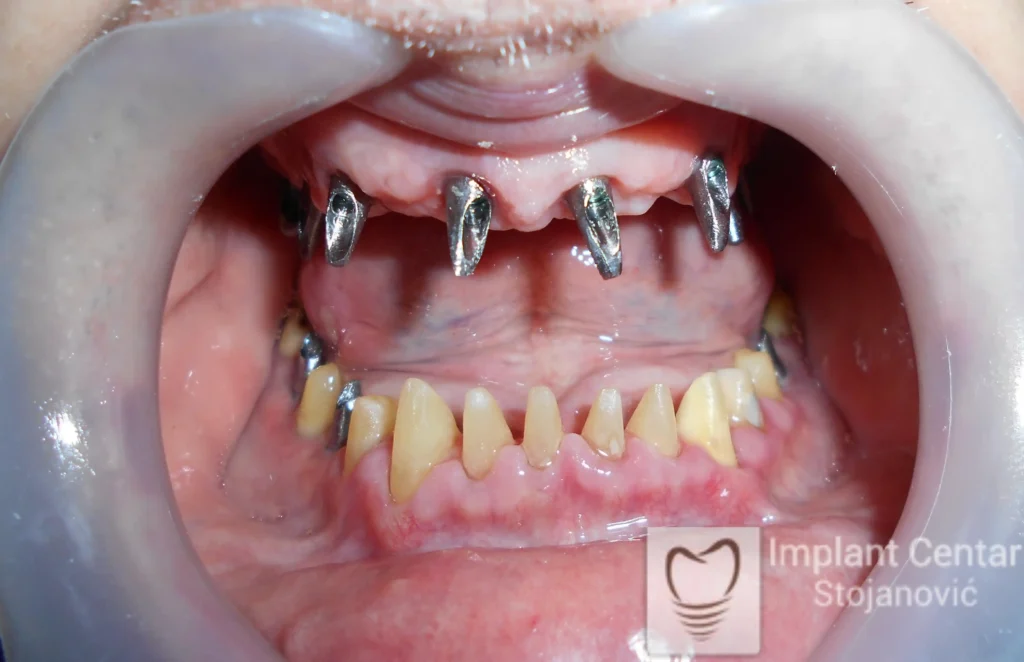

Nakon detaljnog kliničkog pregleda i analize radioloških snimaka, izrađen je sveobuhvatan plan terapije sa ciljem uklanjanja mobilnih proteza i postizanja maksimalne funkcionalne i estetske rehabilitacije. Zbog loše biološke vrednosti preostalih zuba, doneta je odluka o njihovom vađenju i ugradnji dentalnih implantata.

Poseban terapijski izazov predstavljalo je premošćavanje defekta nastalog usled rascepa, kao i ograničena količina raspoložive kosti u gornjoj vilici. Primenom većeg broja implantata i odgovarajućih procedura nadoknade kosti, postignuta je stabilna osnova za fiksni protetski rad.

Tokom perioda oseointegracije, pacijent je bio zbrinut fiksnim privremenim krunicama, čime je već pet dana nakon intervencije obezbeđena potpuna funkcionalna i estetska rehabilitacija. Nakon završetka perioda integracije implantata, izrađeni su definitivni cirkonijum-keramički mostovi na implantatima.